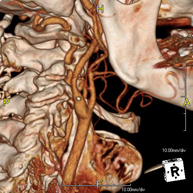

- Angio – TC Troncos Supraaórticos

Prueba radiológica que consiste en obtener imágenes de las arterias carótidas del cuello de alta definición anatómica mediante el empleo de un equipo de TC (Tomografía Computarizada) y la inyección de contraste intravenoso. Posteriormente, las imágenes son reconstruidas en tres dimensiones (3D). Indicaciones: accidente vascular cerebral agudo, accidente vascular transitorio, soplo carotídeo.